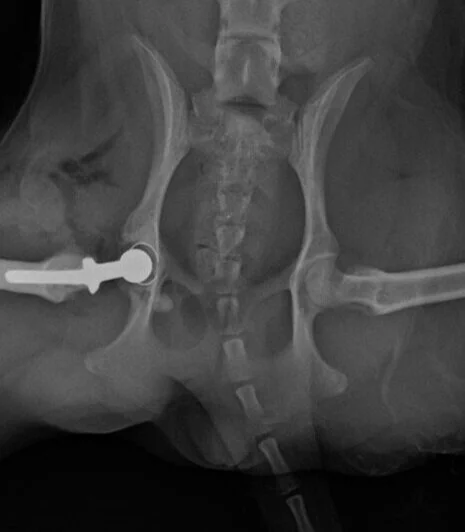

. We also dont have the 400 dollars for that. Femoral head ostectomy or FHO is a surgical procedure in which the top portion of the femur thigh bone is removed. The cost of your cats FHO surgery will depend upon a.

Animal owner restrictions might preclude THR surgery. What is the success rate of FHO surgery. FHO Surgery Dog- Cost FHO surgery is a relatively inexpensive procedure that can often help to restore pain-free mobility to smaller dogs.

Although some bone fractures can be pinned into place without issue in other instances -- such as severe damage to the hip or pelvis -- femoral head ostectomy FHO is. Femoral Head Ostectomy. She then suggested we take a sample of the fluid to see if its an infection.

FHO surgery is a relatively inexpensive procedure that can often help to restore pain-free mobility to cats and smaller dogs. Cat After FHO Surgery - What to Expect. Every cat is different.

The cost of your dogs surgery will. Small dogs and cats do not necessarily do better than large dogs after a FHO. FHO generally results in reasonable function in most patients.